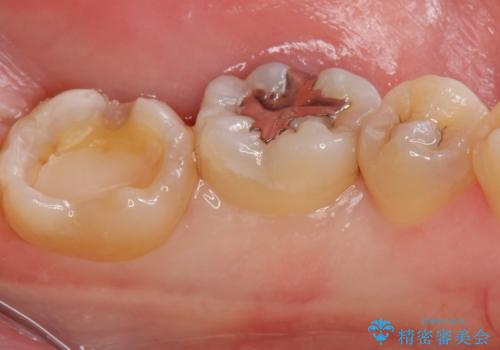

- 矯正を考えている患者様です。

歯の噛む面(咬合面)に虫歯が見られたので拡大鏡下で除去し

白い詰め物(e-maxインレー)にて治療しました。